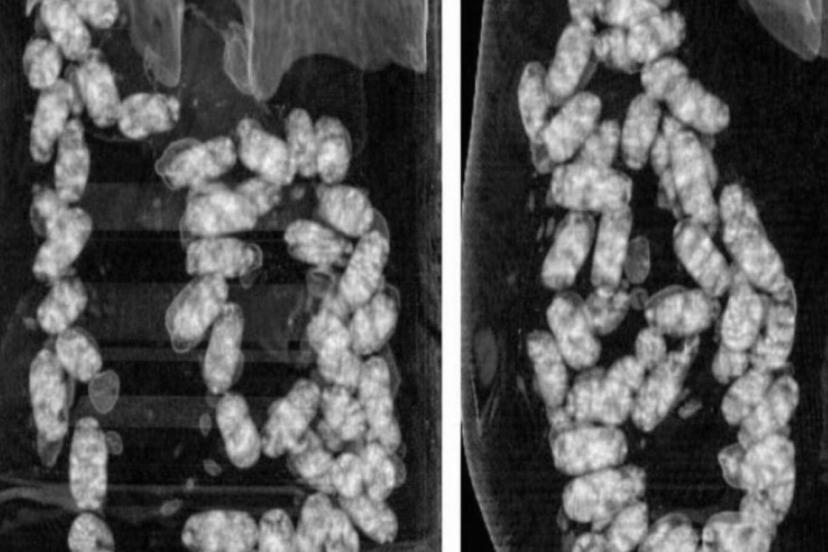

Narkotik Suçlarla Mücadele Şube Müdürlüğü ekiplerince yurt dışından İzmir’e "yutmak" suretiyle uyuşturucu madde getirilmesi üzerine operasyon başlatıldı.

Yapılan teknik ve fiziki takip sonucunda kimlikleri tespit edilen şahıslar, İzmir Adnan Menderes Havalimanı’nda yakalandı.

Şüpheliler üzerinde yapılan iç beden muayenesinde, 105 kapsül halinde yutulmuş vaziyette toplam 965 gram metamfetamin ele geçirildi.

Operasyon kapsamında gözaltına alınan iki şüpheli emniyetteki işlemlerinin ardından sevk edildikleri mahkemece tutuklandı.